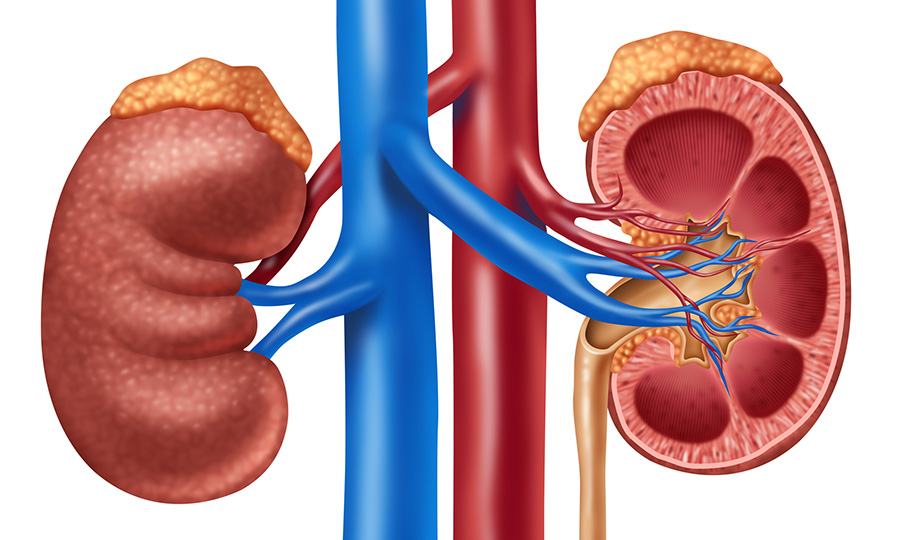

Una campagna di sensibilizzazione globale volta ad aumentare l’informazione sull’importanza dei nostri reni e si svolge ogni anno da 13 anni in tutto il mondo, prevedendo...